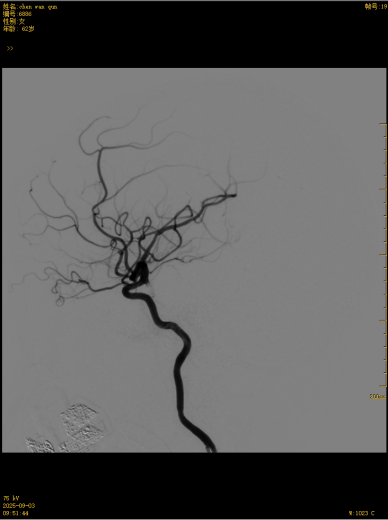

这款国产创新技术的优势不止于疗效:通体显影设计让支架定位精准到毫米级;超弹性材质与优化编织工艺实现极致贴壁,兼顾支撑力与柔顺性,适配复杂迂曲脑血管;操作更轻巧、创伤更小,仅需大腿根部米粒大小切口即可完成手术,可实现患者术后可快速康复。本次手术中,团队在DSA引导下精准释放支架,全程耗时短、出血少,术后造影显示,动脉瘤内血流即刻变得迟缓,载瘤动脉通畅,重要分支血管保护完好。患者术后恢复良好,未出现任何神经功能障碍,术后不久即快速康复出院,重获健康,恢复正常生活工作。